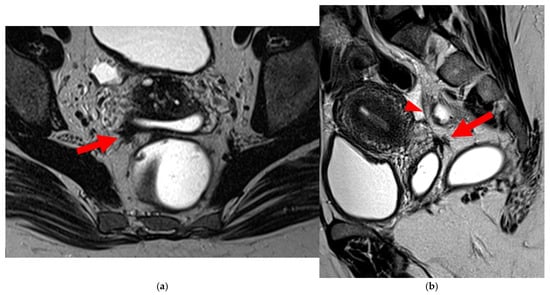

2.3.1. “Kissing Ovaries”: A Form Straddling Between Type 5B and Type 6 USLs

Besides endometriomas, another type of ovarian involvement in DIE includes adhesions that cause the ovaries to retract medially across the midline, behind the uterus, into the pouch of Douglas. When the ovaries are displaced medially and are in close proximity, they are commonly referred to as “kissing ovaries”. Additionally, medialized ovaries on preoperative imaging expose the digestive tract to a 20% risk of involvement [22]. In our experience, the injection of a contrast agent is useful when there is doubt about an endometriotic rectosigmoid invasive lesion on T2WI, especially if a rectal filling was not performed. A markedly enhancing mucosa, which outlines rectosigmoid local wall thickening on post-contrast T1WI without fat suppression (forming a “medallion-shaped” lesion), is a valuable aid to diagnosis.

In the HTD MRI classification of USLs, the “kissing ovaries” sign is considered a form between types 5B and 6. In the case of concomitant rectal involvement, the USL is classified as type 6 (Figure 15); otherwise, it is classified as type 5B (comparable to a nodule with spiculated margins).

Figure 15. Pelvic MRI scan of a patient with a “kissing ovaries” sign and rectal involvement (i.e., HTD type 6 USLs). (a,b) Axial T2WI (a) and contrast-enhanced T1WI (b) show both ovaries in close proximity (“kissing ovaries” sign) (arrowheads) and rectosigmoid wall infiltration (arrows). (c) Sagittal contrast-enhanced T1WI shows rectosigmoid wall infiltration, appearing as a “medallion-shaped” lesion outlined by markedly enhancing mucosa (arrowhead).